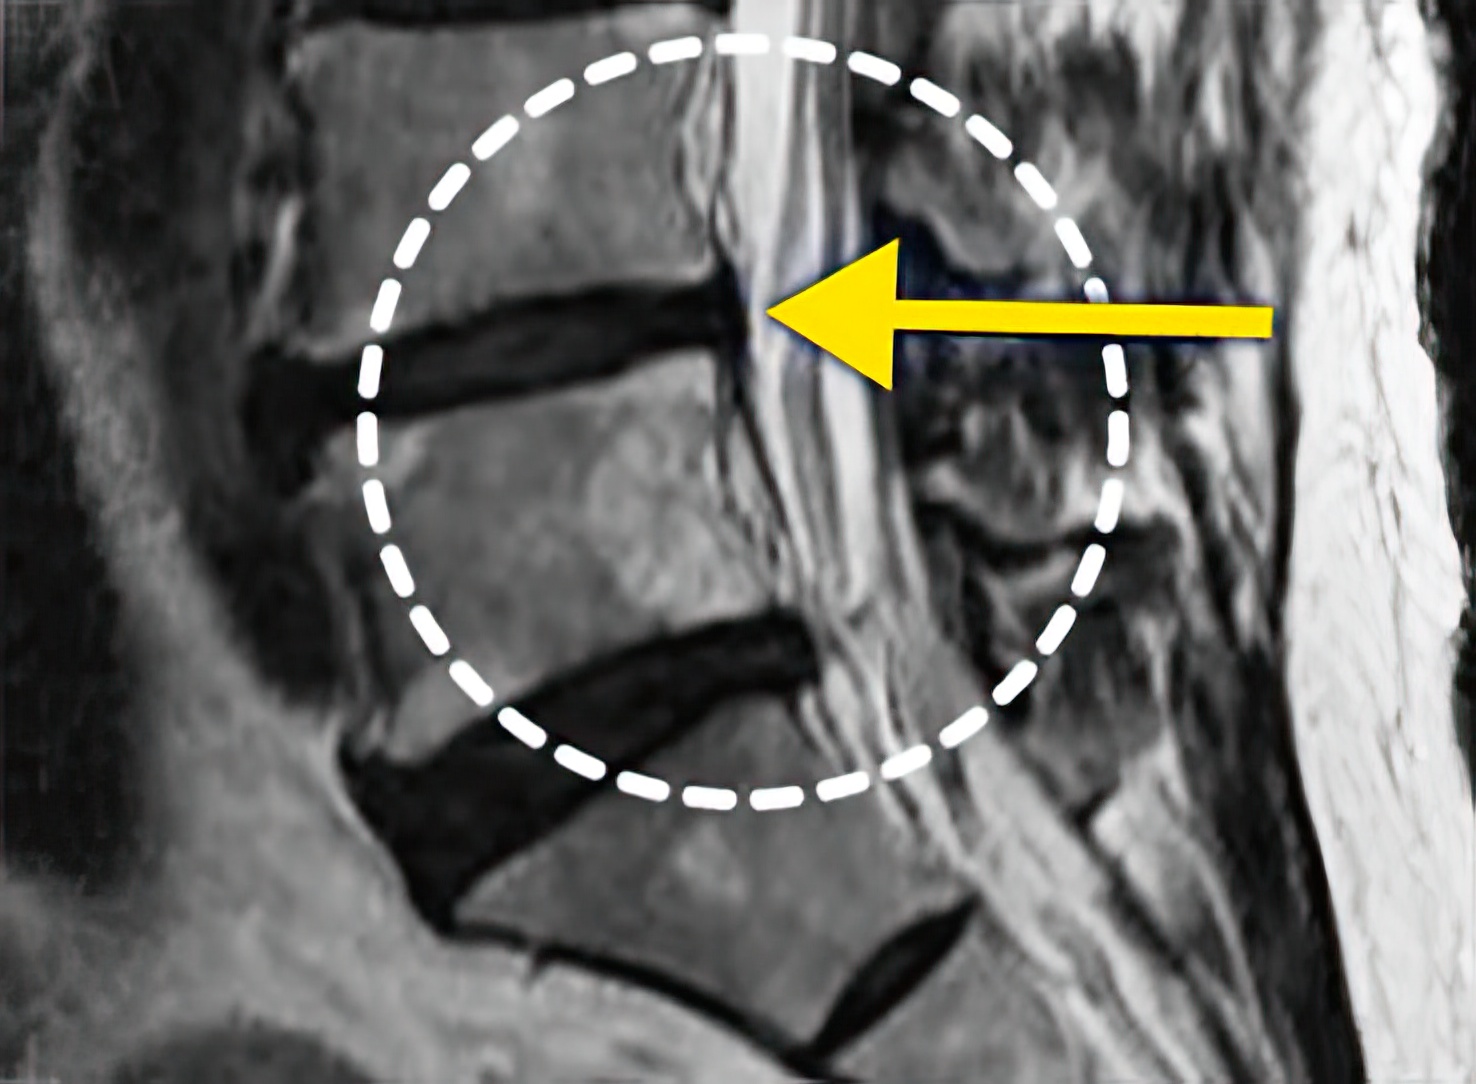

오랜 시간 동안 진행되어온 퇴행성 척추질환(퇴행성디스크, 척추관 협착증), 뼈의 구조적인 이상(척추분리증, 척추전방전위증, 척추이분증) 등은 병의 진행 상태에 따라 치료 기간이 달라질 수 있습니다.